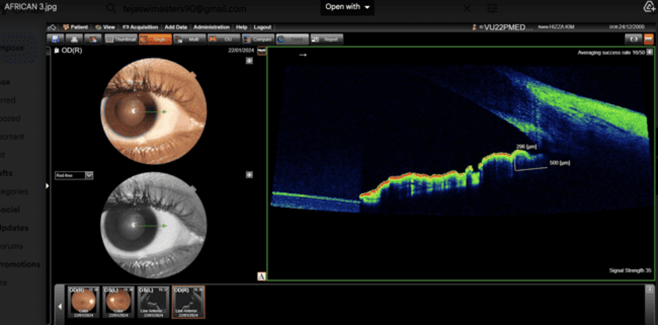

Volunteers Asians and Africans students selected from paramedical courses Gitam University, Visakhapatnam campus. In this analytical comparative  study, 400 eyes (100 Asians and 100 Africans), between the age of 18 to 35 years are selected for this study. Out  of 100 subjects  50 are males and 50 are females from Asian ethnicity and African ethnicity respectively. A comprehensive ophthalmic examination is carried out, includes Best Corrected visual acuity (BCVA) obtained after refractive correction, Anterior segment is evaluated by Slit lamp biomicroscopic examination, Fundus examination is carried out by + 78Ds lens,  Intra Ocular Pressure (IOP) recorded with Applanation tonometer. The cases with defective vision, IOP more than 21 mm of Hg, those who underwent LASIK, other Anterior segment diseases are excluded from this study. This study is conducted in the Department of Ophthalmology with the approval of Ethics committee of  Gitam Institute of Medical Sciences and Research, Visakhapatnam. All the cases are subjected to measurement of root of iris by the Optical coherent tomograph Topcon 3D OCT-1 Maestro 2 in static mode, 500 microns from the root of the iris. Nasal aspects of the root of the iris thickness of the Africans (Fig 1) and Asians are measured (Fig 2).

Fig 1: Iris thickness of African at T500 with 296 microns

Fig 2: Fig: Iris thickness of Asian at T500 with 325 microns